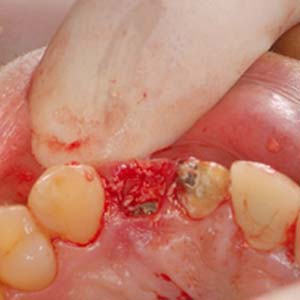

拔除殘留牙根

測量角度與深度

置入適當位置

骨缺損處,置放骨粉

當日在拔除牙齒後,立即在拔牙窩洞裡,置入適當尺寸的植體,並在使用人工骨粉填塞縫隙。